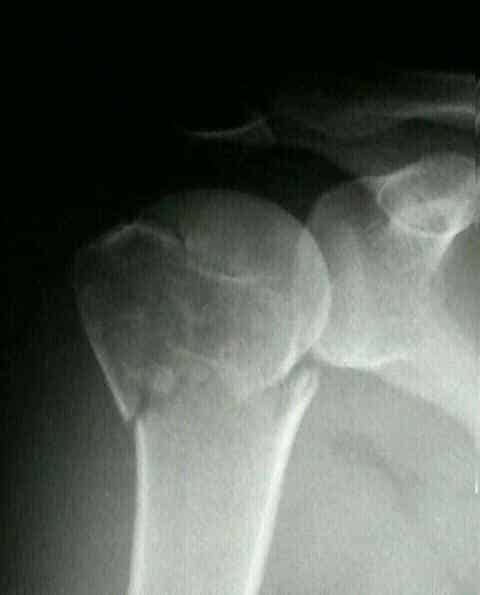

Самая информативная процедура — рентген. Снимки выполняют в двух проекциях — аксиальной, сверху вниз через подкрыльцовую ямку, и в прямой. Дополнительно, при необходимости уточнения данных по травме, может быть назначена компьютерная томография.

Внутрисуставные переломы подтверждают на ультразвуковом исследовании. Снимки плечевой кости в аксиальной проекции устанавливают наличие боковых смещений отломка. Рентгеновские фото помогают диагностировать и отличить вколоченный перелом плечевой кости от невколоченного.